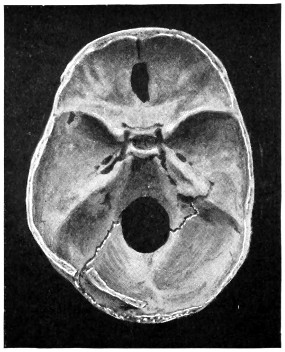

29 A and B. The base of the skull and the base as seen on transillumination 70, 71

30. Plan of the base of the skull 77